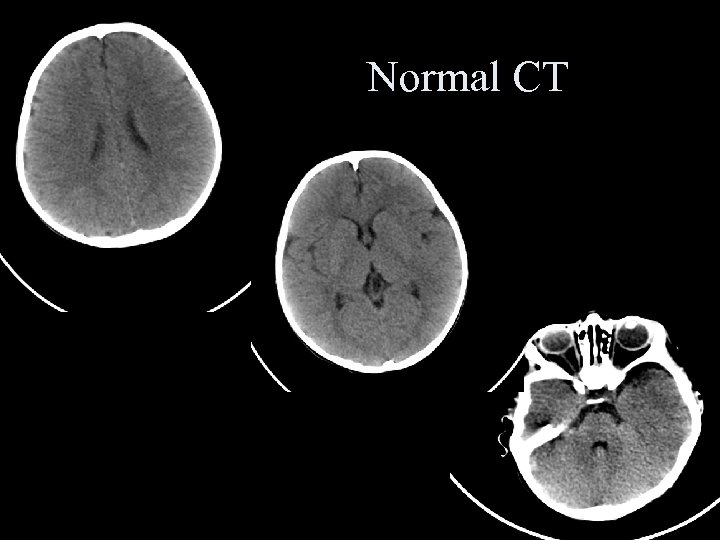

Normal CT Normal CT